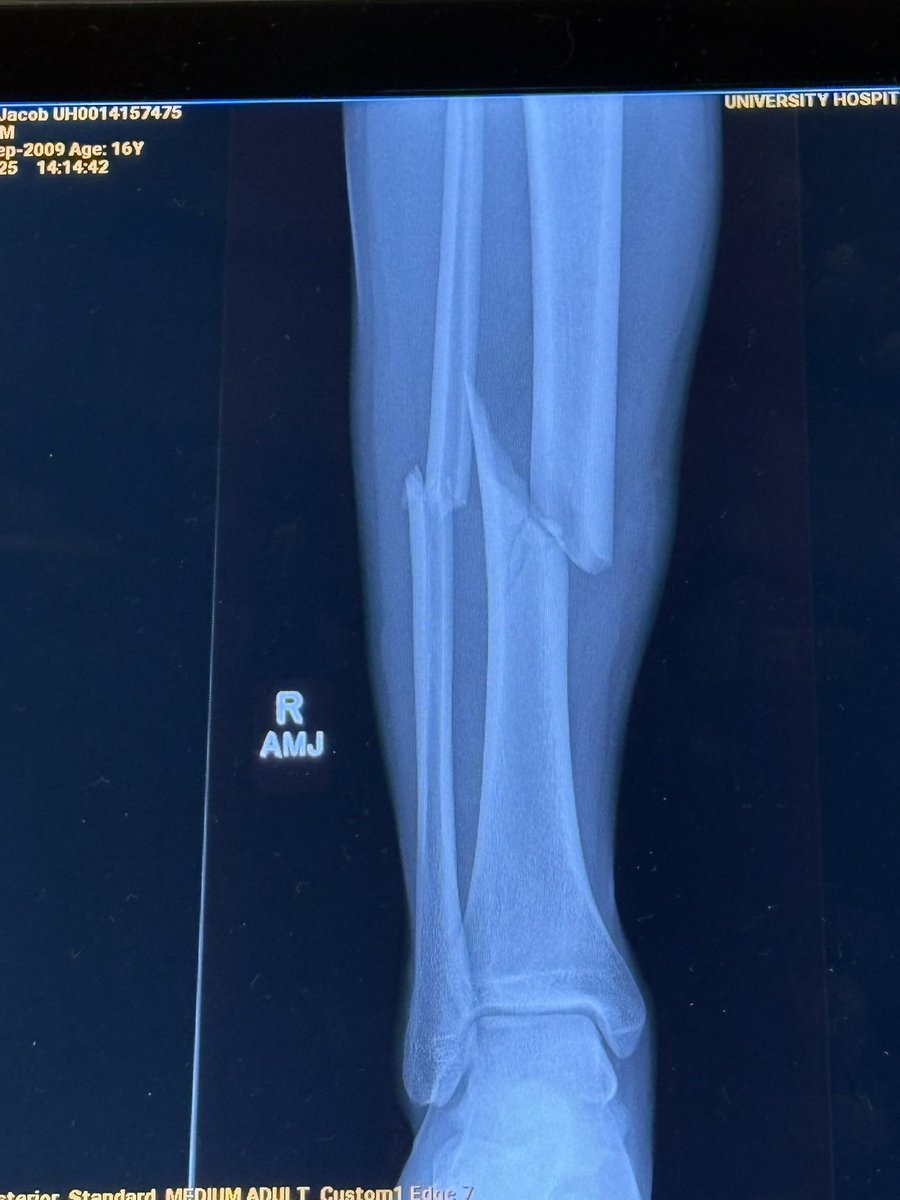

15 Weeks Post Leg Reconstruction!!!